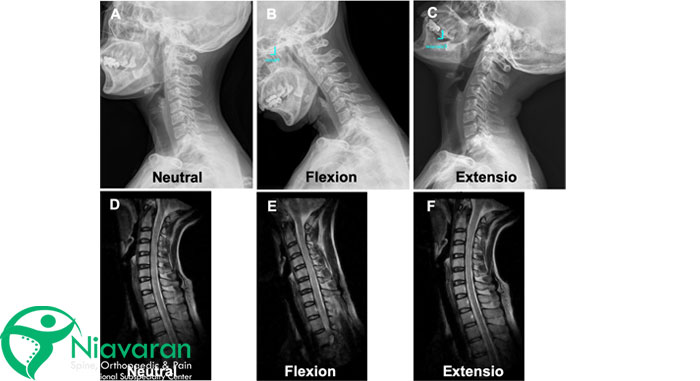

mr گردن برای چیست؟ ام آر آی گردن (Cervical Spine MRI Scan) یک روش تصویربرداری غیرتهاجمی است که برخلاف اشعه ایکس یا سیتیاسکن، از میدان مغناطیسی قوی و امواج رادیویی برای ایجاد تصاویر دقیق از استخوانهای ستون فقرات گردنی، بافتهای نرم و اعصاب اطراف گردن شما بدون خطر قرارگرفتن در معرض تشعشع استفاده میکند. این تصاویر با جزئیات بالا میتوانند به پزشکان در تشخیص و ارزیابی طیف گستردهای از بیماریها و آسیبهای مرتبط با گردن مانند آرتروز گردن، برآمدگی دیسک، فتق دیسک، تومور، آنوریسم و برخی اختلالات خودایمنی کمک کنند.

اگر گردن درد همراه با ضعف، بیحسی یا سوزنسوزنشدن در بازوها، پاها یا دستان شما باشد، این میتواند نشانهای از فشردگی نخاع باشد. همچنین برای تشخیص و ارزیابی آسیبها یا التهاب در بافتهای نرم گردن مانند عضلات، رباطها و تاندونها، برای تشخیص نقایص مادرزادی یا ناهنجاریهای استخوانی در ستون فقرات گردن یا نواحی نزدیک به آن مانند آسیب یا ضربه به ناحیه گردنی، تومور یا عفونت و برای تشخیص و ارزیابی اختلالات مفصلی در گردن، مانند انحنای غیرطبیعی ستون فقرات گردنی یا اسکولیوز پزشک متخصص ام آر ای گردن را پیشنهاد میدهد.

- عملکرد بهتر در تصویربرداری از بافتهای نرم؛ مانند عضلات، رباطها، تاندونها، دیسکها و مایع مغزی نخاعی و تشخیص آسیبها یا التهاب در این بافتها

- ارائه اطلاعات و تصاویر چندبعدی از ستون فقرات گردنی شما برای درک بهتر آناتومی و عملکرد آن توسط پزشکان و نهایتاً تشخیص و درمان دقیقتر

تفسیر جواب ام آر ای گردن میتواند یک فرایند پیچیده باشد که به تخصص و تجربه پزشکی قابلتوجهی نیاز دارد. برای درک صحیح تصاویر ام آر آی، ضروری است که پزشک از آناتومی پیچیده ستون فقرات گردنی و ساختارهای اطراف آن آگاهی کامل داشته باشد. معمولاً طول میکشد تا یک پزشک واجد شرایط، مانند رادیولوژیست، دکتر دیسک گردن یا متخصص مغز و اعصاب، نتایج ام آر آی گردن شما را تفسیر کند.

در طول تفسیر و خواندن mri گردن، آنها به دنبال ناهنجاریهایی مانند فتق دیسک، تنگی کانال نخاعی، آرتروز، تومور یا آسیب به استخوانها، عضلات یا رباطهای گردن شما خواهند بود. تفسیر MRI گردن باید در کنار سایر یافتههای بالینی، مانند سابقه پزشکی، معاینه فیزیکی و نتایج سایر آزمایشات، انجام شود تا تصویر کاملی از وضعیت بیمار ارائه شود.